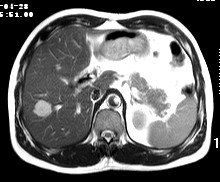

标题: CT19720:肝右叶血管瘤。肝左叶内侧段病灶考虑什么? [打印本页]

标题: CT19720:肝右叶血管瘤。肝左叶内侧段病灶考虑什么?

男,48岁,肝区不适月余,伴隐痛。

支持右叶血管瘤,左叶病灶考虑肝腺瘤。

1)不排除肝左叶肝癌。2)肝右叶血管瘤。

肝左叶炎性病变,肝癌待排。2)肝右叶血管瘤。

1.肝右叶血管瘤;2.肝左叶炎性假瘤?肝癌?建议穿刺活检.

右叶病灶典型,左叶病变慢性炎块

1、肝右叶血管瘤(典型)。

2、肝左叶病灶,强化不明显,疑炎性假瘤,建议结合临床并密切随访。

1、肝左叶炎性病变,肝癌待排。

2、肝右叶血管瘤。

肝左叶脓肿,肝癌待排。2)肝右叶血管瘤